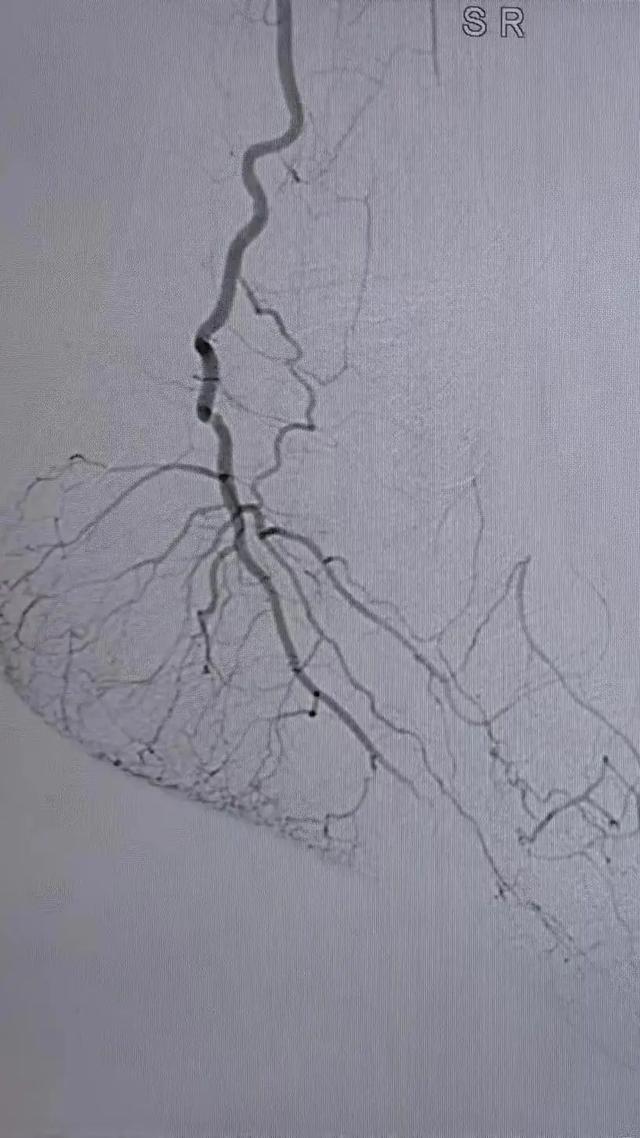

术中选用Rotarex导管行血栓清除,对管腔内残留的血栓放置溶栓导管,最后采用球囊扩张狭窄病变,管腔获得满意。

治疗后者患者肢体、疼痛缓解,无远端血管栓塞,无缺血再灌注损伤,3日后顺利出院。